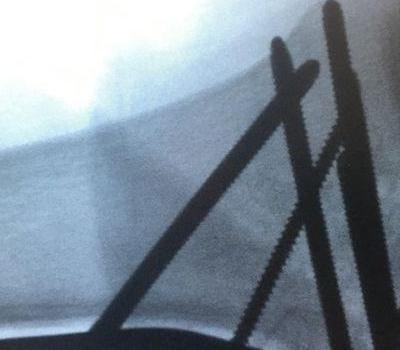

Galeria Przepuklina dysku międzykręgowego L4-L5 Przepuklina dysku międzykręgowego L4-L5 Operacja mikrochirurgicznego usunięcia przepukliny dysku międzykręgowego Operacja mikrochirurgicznego usunięcia przepukliny dysku międzykręgowego Operacja dyskopatii L5-S1 - dyscektomia, stabilizacja międzytrzonowa TLIF i przeznasadowa przy użyciu nawigacji Operacja dyskopatii L5-S1 - dyscektomia, stabilizacja międzytrzonowa TLIF i przeznasadowa przy użyciu nawigacji Operacja dyskopatii L5-S1 - dyscektomia, stabilizacja międzytrzonowa TLIF i przeznasadowa przy użyciu nawigacji Kręgozmyk cieśniowy L4-L5 Kręgozmyk cieśniowy L4-L5 Operacja kręgozmyku L4-L5 - osteotomia tylnej kolumny kręgosłupa, dyscektomia, stabilizacja międzytrzonowa TLIF typu "banan" i stabilizacja przeznasadowa - widoczny odbarczony worek oponowy i korzenie nerwowe Operacja kręgozmyku L4-L5 - osteotomia tylnej kolumny kręgosłupa, dyscektomia, stabilizacja międzytrzonowa TLIF typu "banan" i stabilizacja przeznasadowa Operacja kręgozmyku L4-L5 - osteotomia tylnej kolumny kręgosłupa, dyscektomia, stabilizacja międzytrzonowa TLIF typu "banan" i stabilizacja przeznasadowa Operacja kręgozmyku L4-L5 - osteotomia tylnej kolumny kręgosłupa, dyscektomia, stabilizacja międzytrzonowa TLIF typu "banan" i stabilizacja przeznasadowa Operacja kręgozmyku L4-L5 - osteotomia tylnej kolumny kręgosłupa, dyscektomia, stabilizacja międzytrzonowa TLIF typu Operacja kręgozmyku L4-L5 - osteotomia tylnej kolumny kręgosłupa, dyscektomia, stabilizacja międzytrzonowa TLIF typu Operacja małoinwazyjna guza przerzutowego kręgosłupa piersiowo -lędźwiowego -przezskórna stabilizacja przeznasadowa Operacja małoinwazyjna guza przerzutowego kręgosłupa piersiowo -lędźwiowego -przezskórna stabilizacja przeznasadowa Operacja małoinwazyjna guza przerzutowego kręgosłupa piersiowo -lędźwiowego -przezskórna stabilizacja przeznasadowa - obraz z systemu nawigacji Operacja małoinwazyjna guza przerzutowego kręgosłupa piersiowo -lędźwiowego -przezskórna stabilizacja przeznasadowa Operacja małoinwazyjna guza przerzutowego kręgosłupa piersiowo -lędźwiowego -przezskórna stabilizacja przeznasadowa Operacja małoinwazyjna guza przerzutowego kręgosłupa piersiowo -lędźwiowego -przezskórna stabilizacja przeznasadowa Operacja skoliozy Operacja skoliozy Deformacja kręgosłupa u osoby dorosłej - przed operacją Deformacja kręgosłupa u osoby dorosłej - po operacji Skolioza idiopatyczna dorastających - przed operacją Skolioza idiopatyczna dorastających - po operacji Pogłębiona bolesna kifoza w chorobie Scheuermanna - przed operacją Pogłębiona bolesna kifoza w chorobie Scheuermanna - po operacji korekcyjnej z wielopoziomową osteotomią kręgosłupa piersiowego Pogłębiona bolesna kifoza w chorobie Scheuermanna - przed operacją - inny pacjent - oznaczenia miejsc "nacięcia" - osteotomii kręgosłupa piersiowego Pogłębiona bolesna kifoza w chorobie Scheuermanna - przed operacją - inny pacjent Pogłębiona bolesna kifoza w chorobie Scheuermanna - po operacji korekcyjnej z wielopoziomową osteotomią kręgosłupa piersiowego Operacja przezskórnej stabilizacji złamania kręgosłupa implantem dotrzonowym Operacja przezskórnej stabilizacji złamania kręgosłupa implantem dotrzonowym Operacja przezskórnej stabilizacji złamania kręgosłupa implantem dotrzonowym Operacja przezskórnej stabilizacji złamania kręgosłupa implantem dotrzonowym Operacja przezskórnej stabilizacji złamania kręgosłupa implantem dotrzonowym Operacja przezskórnej stabilizacji złamania kręgosłupa implantem dotrzonowym Operacja przezskórnej stabilizacji złamania kręgosłupa implantem dotrzonowym Operacja przezskórnej stabilizacji złamania wybuchowego kręgu L1 pod kontrolą śródoperacyjnej tomografii komputerowej Operacja przezskórnej stabilizacji złamania wybuchowego kręgu L1 pod kontrolą śródoperacyjnej tomografii komputerowej Operacja przezskórnej stabilizacji złamania wybuchowego kręgu L1 pod kontrolą śródoperacyjnej tomografii komputerowej - rany po zabiegu Endoprotezoplastyka stawu biodrowego w chorobie zwyrodnieniowej Zabieg artrodezy (usztywnienia) uszkodzonego stawu skokowo -piętowego Zabieg artrodezy (usztywnienia) uszkodzonego stawu skokowo -piętowego Zabieg artrodezy (usztywnienia) uszkodzonego stawu skokowo -piętowego Hallux valgus- paluch koślawy - przed operacją Hallux valgus- paluch koślawy - po operacji korekc Znacznego stopnia przemieszczone śródstawowe złamanie kości piszczelowej - TK przed operacją Znacznego stopnia przemieszczone śródstawowe złamanie kości piszczelowej - TK przed operacją Znacznego stopnia przemieszczone śródstawowe złamanie kości piszczelowej - TK przed operacją Operacja nastawienia złamania i stabilizacji implantem wewnętrznym -płytą blokowaną i śrubami Operacja nastawienia złamania i stabilizacji implantem wewnętrznym -płytą blokowaną i śrubami Operacja nastawienia złamania i stabilizacji implantem wewnętrznym -płytą blokowaną i śrubami